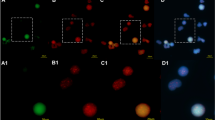

Changes in telomere length depending on CML phase and BCR::ABL1 expression level in CD34+ primary leukemic cells isolated from patients at different stages of disease (CML-CP and CML-BP). a Interphase and metaphase FISH images with typical BCR::ABL1 gene rearrangements observed among the study groups using LSI BCR/ABL1 probe localized on chr.22q11.2 and chr.9q34, respectively (signal pattern 2F1R1G). Sequences flanking the ABL1 (9q34) gene are direct labeled with PlatinumBright™550. Sequences flanking the BCR (22q11) gene are direct-labeled PlatinumBright™495. b The BCR::ABL1 expression level normalized to B2M and GUSB measured with qPCR (non-parametric Student’s t test and Mann–Whitney post-test) ***p < 0.001, n = 71. c Representative images from Southern blot analysis. Mean TRF length (kbp) is shown in the legend of the particular lanes. Lanes: 1 and 15 DIG-molecular weight marker (MWM), [0.8–21.2], 2 and 15 control DNA [7.6 ± 0.2] (PC). d Comparison of telomere length measured by TRF method in leukocytes isolated from healthy donors (N) and patients at different stages of disease: CML-CP, CML-BP expressed as kbp, (ANOVA and Tukey’s a posteriori test). ***p < 0.001, *p < 0.05, n = 47. e Correlation between the level of mRNA BCR::ABL1 expression and telomere length measured by TRF method (Pearson’s (r) p < 0.05). f Representative microphotographs of Q-FISH for CML CD34 + primary cells isolated from CML-CP, CML-BP patients. Telomere PNA FISH kit/Cy3 (Dako) was used for telomere labeling. Nuclei were counterstained by DAPI. g Means of telomere area (pixel per spot) per CML CD34 + primary cell isolated from CML-CP, CML-BP patients measured by Q-FISH with PNA technique, (non-parametric student t test and Mann–Whitney post-test). **p < 0.01, n = 30. h Correlation between level of mRNA BCR::ABL1 expression and telomere length measured by Q-FISH method (Pearson’s (r) p < 0.05). i Correlation between age and telomere length. (Pearson’s (r) p < 0.05), n = 43. Red dots—CML-BP cells, black dots—CML-CP cells. j Southern blot analysis of telomere length in murine myeloid 32D clone 3: parental and transfected with the BCR::ABL1 gene, MWM—molecular weight marker, PC—positive control. Densitometric profile was performed to correspond to bands of DNA marker using ImageJ with gel analysis module

We decided to verify the model of telomere biology in CML proposed by Brümmendorf et al. on the basis of two techniques, TRF method and Q-FISH analysis, and correlation analysis between obtained results and the level of expression of the BCR::ABL1 gene (Brümmendorf et al. 2000). Additionally, we attempted to explain the phenomenon of changes in telomere length in patients with CML, as observed by Brümmendorf and other researchers. TRF and Q-FISH analysis confirmed that the mean length of telomeres in the CML-BP phase was significantly shorter in comparison with CML-CP phase telomeres (Fig. 1c–g). Moreover, the correlation analysis showed that the dynamics of this process may be related to the level of BCR::ABL1 expression, that is, cells with higher BCR::ABL1 expression had significantly shorter telomeres (Fig. 1e, h). The analysis of the relationship between age of CML patients and mean length of telomeres has shown that telomere length slightly decreased with age (Fig. 1i).

To investigate the effect of BCR::ABL1 tyrosine kinase on telomere length, 32D cells expressing BCR::ABL1, and the parental cell line 32D clone 3 not expressing BCR::ABL1 were compared (Fig. 1j). Telomere lengths were quantified using Southern blot, and the results showed heterogenization of telomere length in BCR::ABL1-expressing and non-expressing cells.